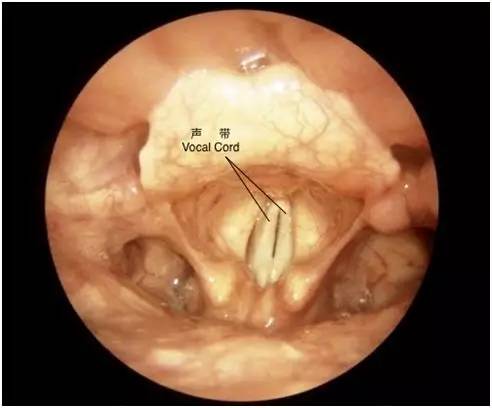

喉位于颈部正中,为图中红色方框标注的位置。它是我们呼吸道的一部分。成年男性有很明显的喉结(“瘦的不明显”的人可能不太容易摸到)。喉腔里面的情况是这样的:

图中两条白色的带状结构即为声带,是我们的发音器官。周围粉红色的部分是黏膜,主要作用是分泌粘液润滑喉腔,同时也通过黏膜免疫机制抵御外界的各种损伤因子。